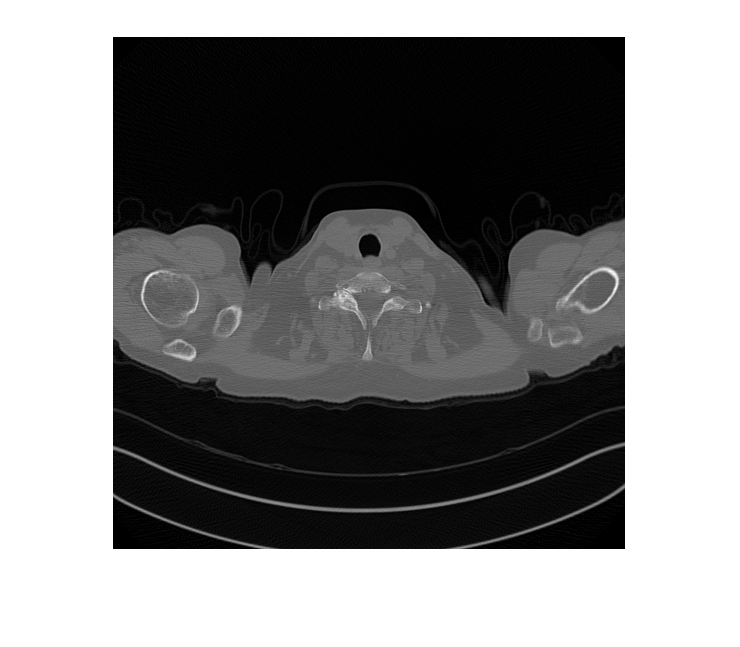

FileExtensions=exts,ReadFcn=readFcn);Предварительно просмотрите учебное изображение от низкой дозы и обучающих наборов данных CT большей дозы.

montage({lowDose,highDose})

Отобразите входной CT низкой дозы, сгенерированную версию большей дозы и изображение большей дозы основной истины в монтаже. Несмотря на то, что сеть обучена на данных из одного терпеливого скана, сеть делает вывод хорошо, чтобы протестировать изображения от других терпеливых сканов.

imshow([imLowDoseTest imHighDoseGenerated imHighDoseGroundTruth]) title(['Low-dose Test Image ',num2str(idxToTest),' with Generated High-dose Image and Ground Truth High-dose Image'])